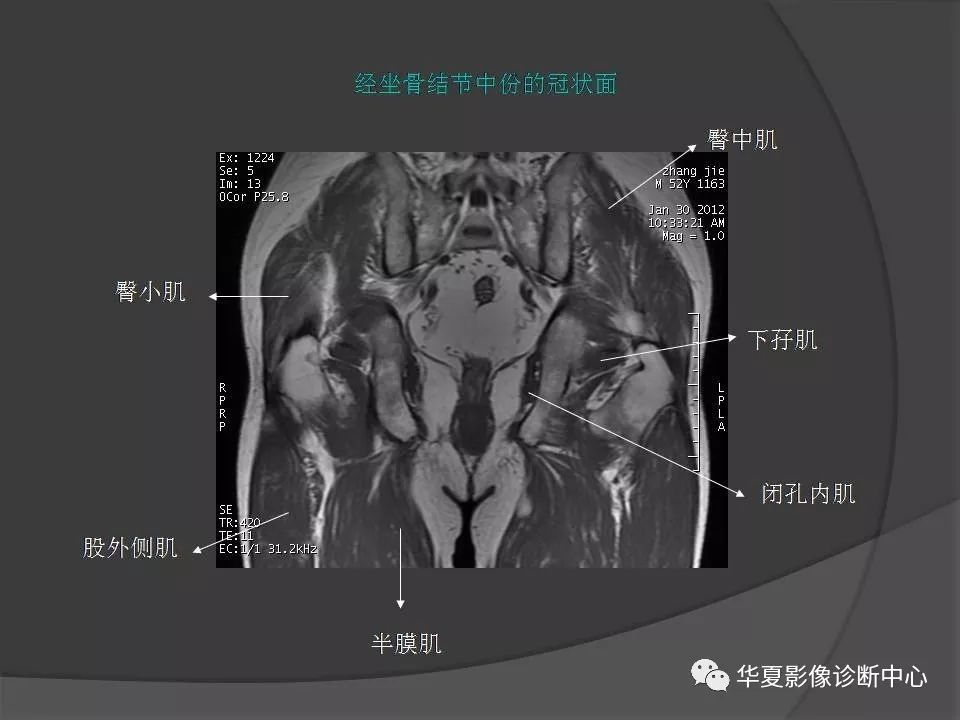

女性盆腔ct连续断层解剖图,盆腔mri影像病例分析